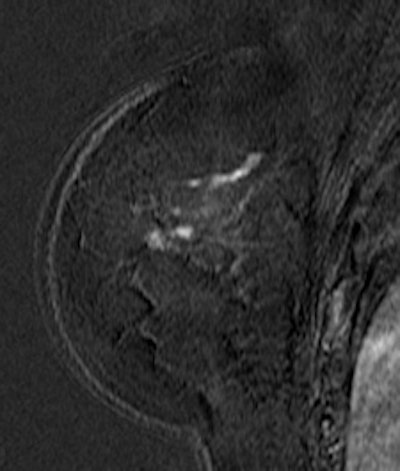

![]() ![]() |

| Patient with breast cancer (invasive ductal carcinoma, grade II). MR-subtracted images (three minutes after contrast medium injection) before (left) and at the end (right) of the neoadjuvant chemotherapy. Initial staging: unifocal infiltrating cancer. After treatment, even if there is a decrease in size of the cancer, its long axis (RECIST) is unchanged with a multifocal shrinkage of the tumor. Unsuccessful first breast-conserving surgery, then mastectomy. Image courtesy of Dr. Anne Tardivon. |